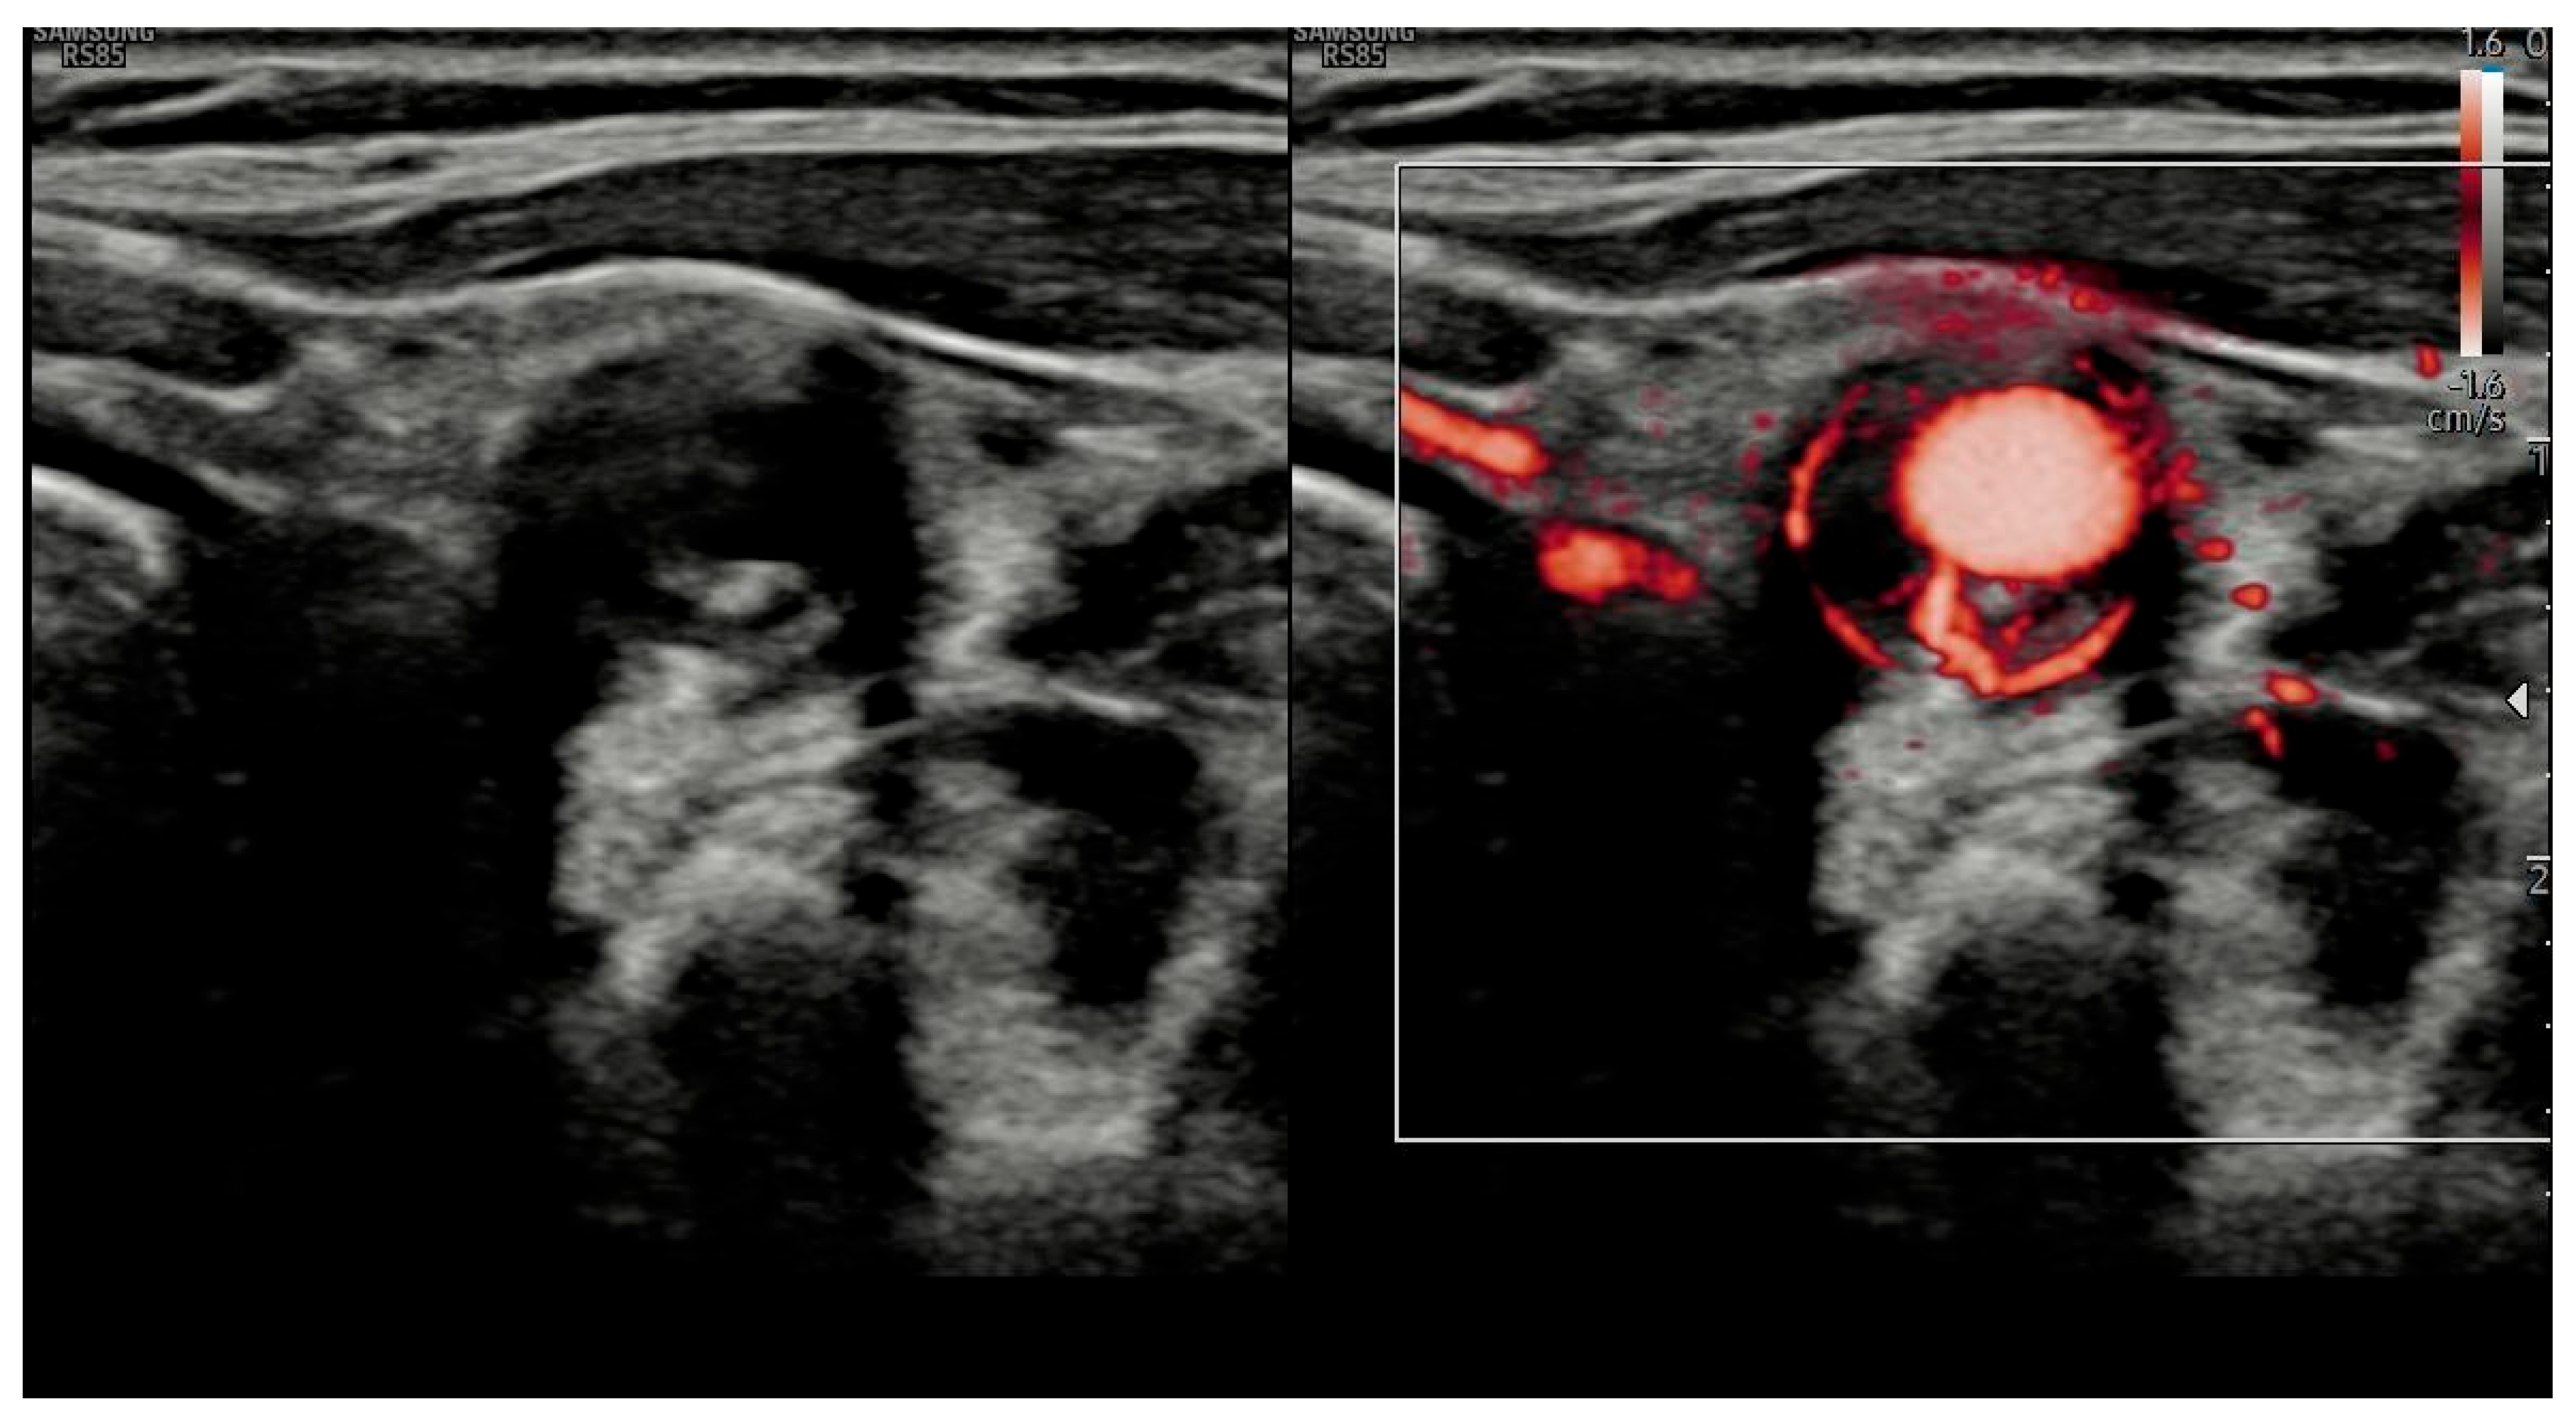

Extended Color Doppler Ultrasound in the Diagnosis of Giant Cell Arteritis: Clinical Insights and Literature Review with Emphasis on Posterior Circulation Involvement

- The use of extended CDUS protocols, including assessment of temporal, axillary, subclavian, carotid and vertebral arteries.

- Kargiotis, O.; Psychogios, K.; Safouris, A.; Bakila, E.; Andreadou, E.; Karapanayiotides, T.; Finitsis, S.; Palaiodimou, L.; Giannopoulos, S.; Magoufis, G.; et al. Cervical duplex ultrasound for the diagnosis of giant cell arteritis with vertebral artery involvement. J. Neuroimaging 2021, 31, 656–664. [Google Scholar] [CrossRef]